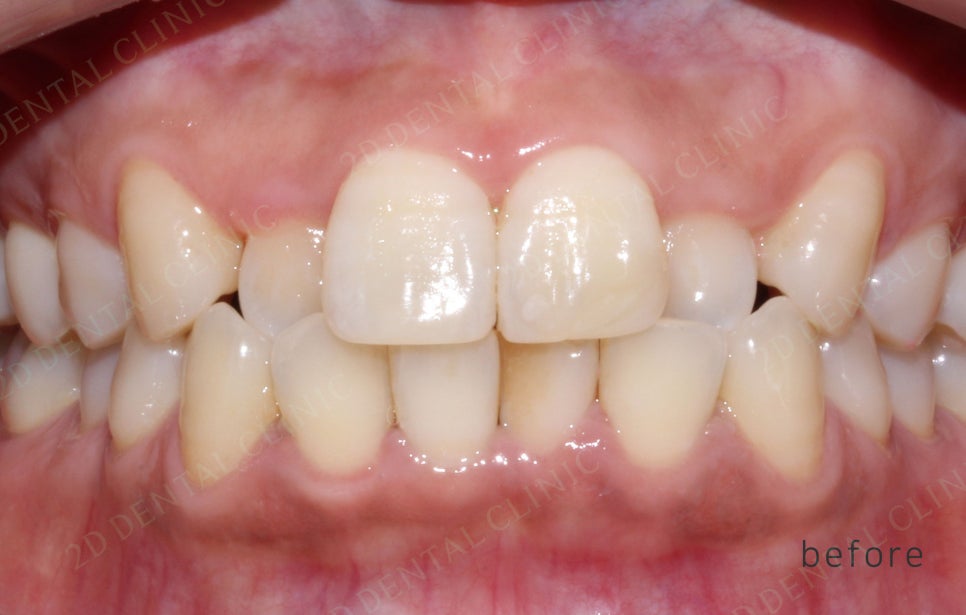

<교정 전/후 >

2D(투디)교정 앞니덧니,반대교합 치아교정

191일(약 6개월)후 투디교정 완료.

전,후 사진만 봐도 치아 배열이 잘

정돈된게 보이시나요!?

치아 배열이 가지런해 지다보니

확실히 입술도 편안해 보이는게 느껴져요♪♪